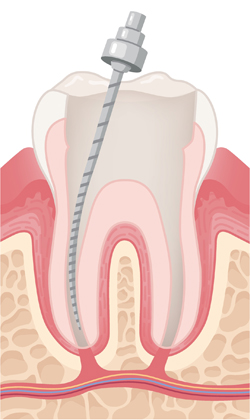

염증이 생긴 신경과 감염된 조직을 제거하고, 뿌리관 내부를 깨끗하게 청소한 뒤 치료에 적합하도록 넓히고 정돈합니다.